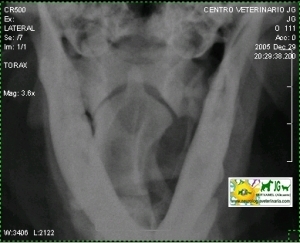

Radiografía digital (no digitalizada) de un cocker inglés mostrando el diente del axis. |